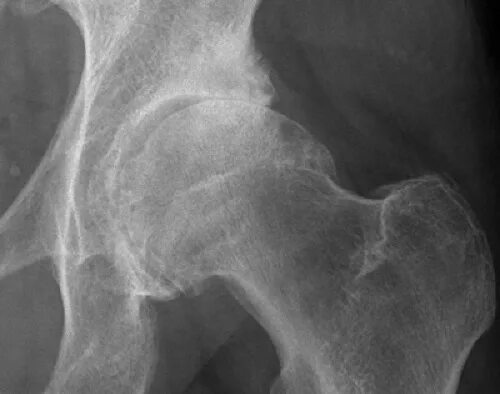

Коксартроз тазобедренного сустава 3